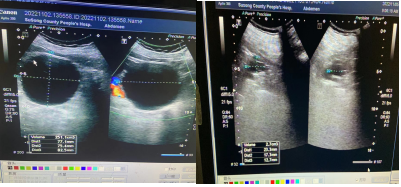

典型病例、右肾囊肿穿刺治疗

治疗前 治疗后